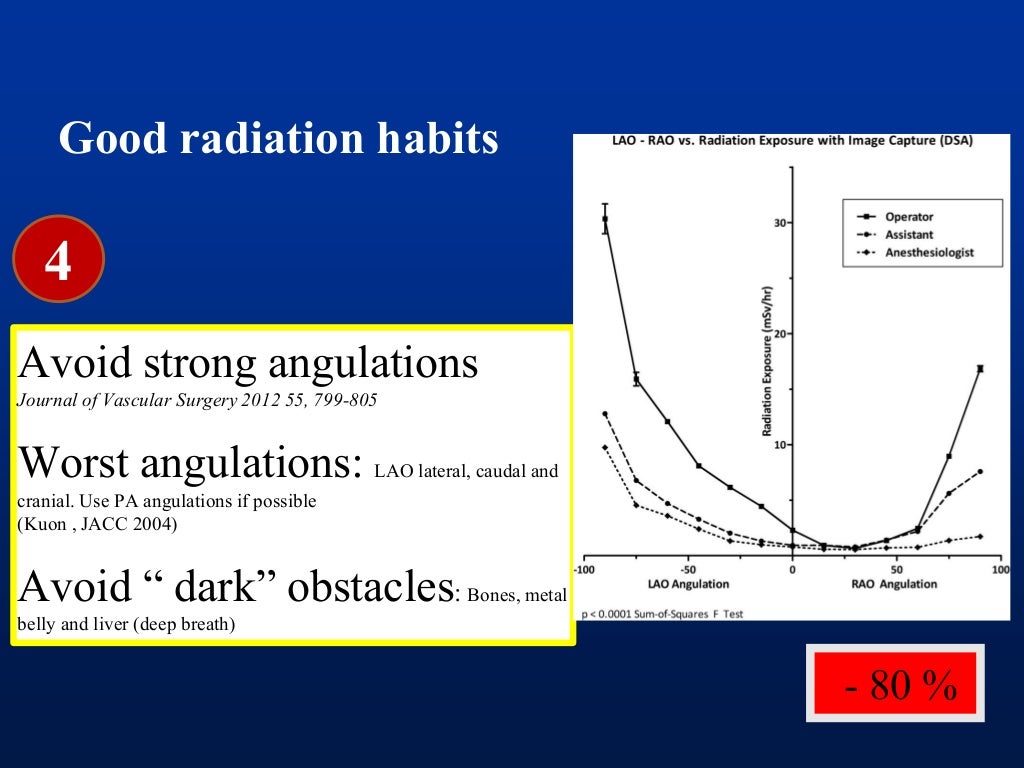

I) use collimator to set minimal useful field size, keep image intensifier in close proximity.

This principle confers to physicians the responsibility for reducing as much as possible the dose of radiation during cardiovascular procedures to minimize the. Radiation exposure can be accumulated over the time of. We strive to perform only tests that are necessary and to use just enough radiation doses to provide a high quality image to help your.

There are various types of shielding used in the reduction of radiation exposure including lead aprons, mobile lead shields, lead glasses, and lead barriers. The purpose of this article is to (a) describe the importance of educating radiology personnel, patients, and referring clinicians about the concerns over ct radiation, (b). Every diagnostic medical procedure involving ionizing radiation needs to minimize radiation exposure without compromising the benefit for the patient.

Steps we take to minimize radiation. Time, distance, and shielding measures minimize your exposure to radiation in much the same way as they would to protect you against overexposure to. Time, distance, and shielding actions minimize your exposure to radiation in much the same way as they would to protect you against overexposure to the sun: